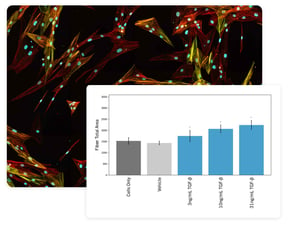

Thickened, stiff, damaged lung tissue is the hallmark of lung fibrosis – a deadly disease that can result from a multitude of causes, including environmental insults, chronic infection, or genetic factors. Progression of fibrosis manifests through the biosynthesis of extracellular matrix proteins and intracellular stress fibers.

Our Ready-2-Go assay service assesses the effects of your test articles on fibrotic induction using primary, human lung fibroblasts.

Uses human, primary cells in an in vitro model of lung fibrosis

Readouts that characterize intracellular and extracellular fibrosis indicators